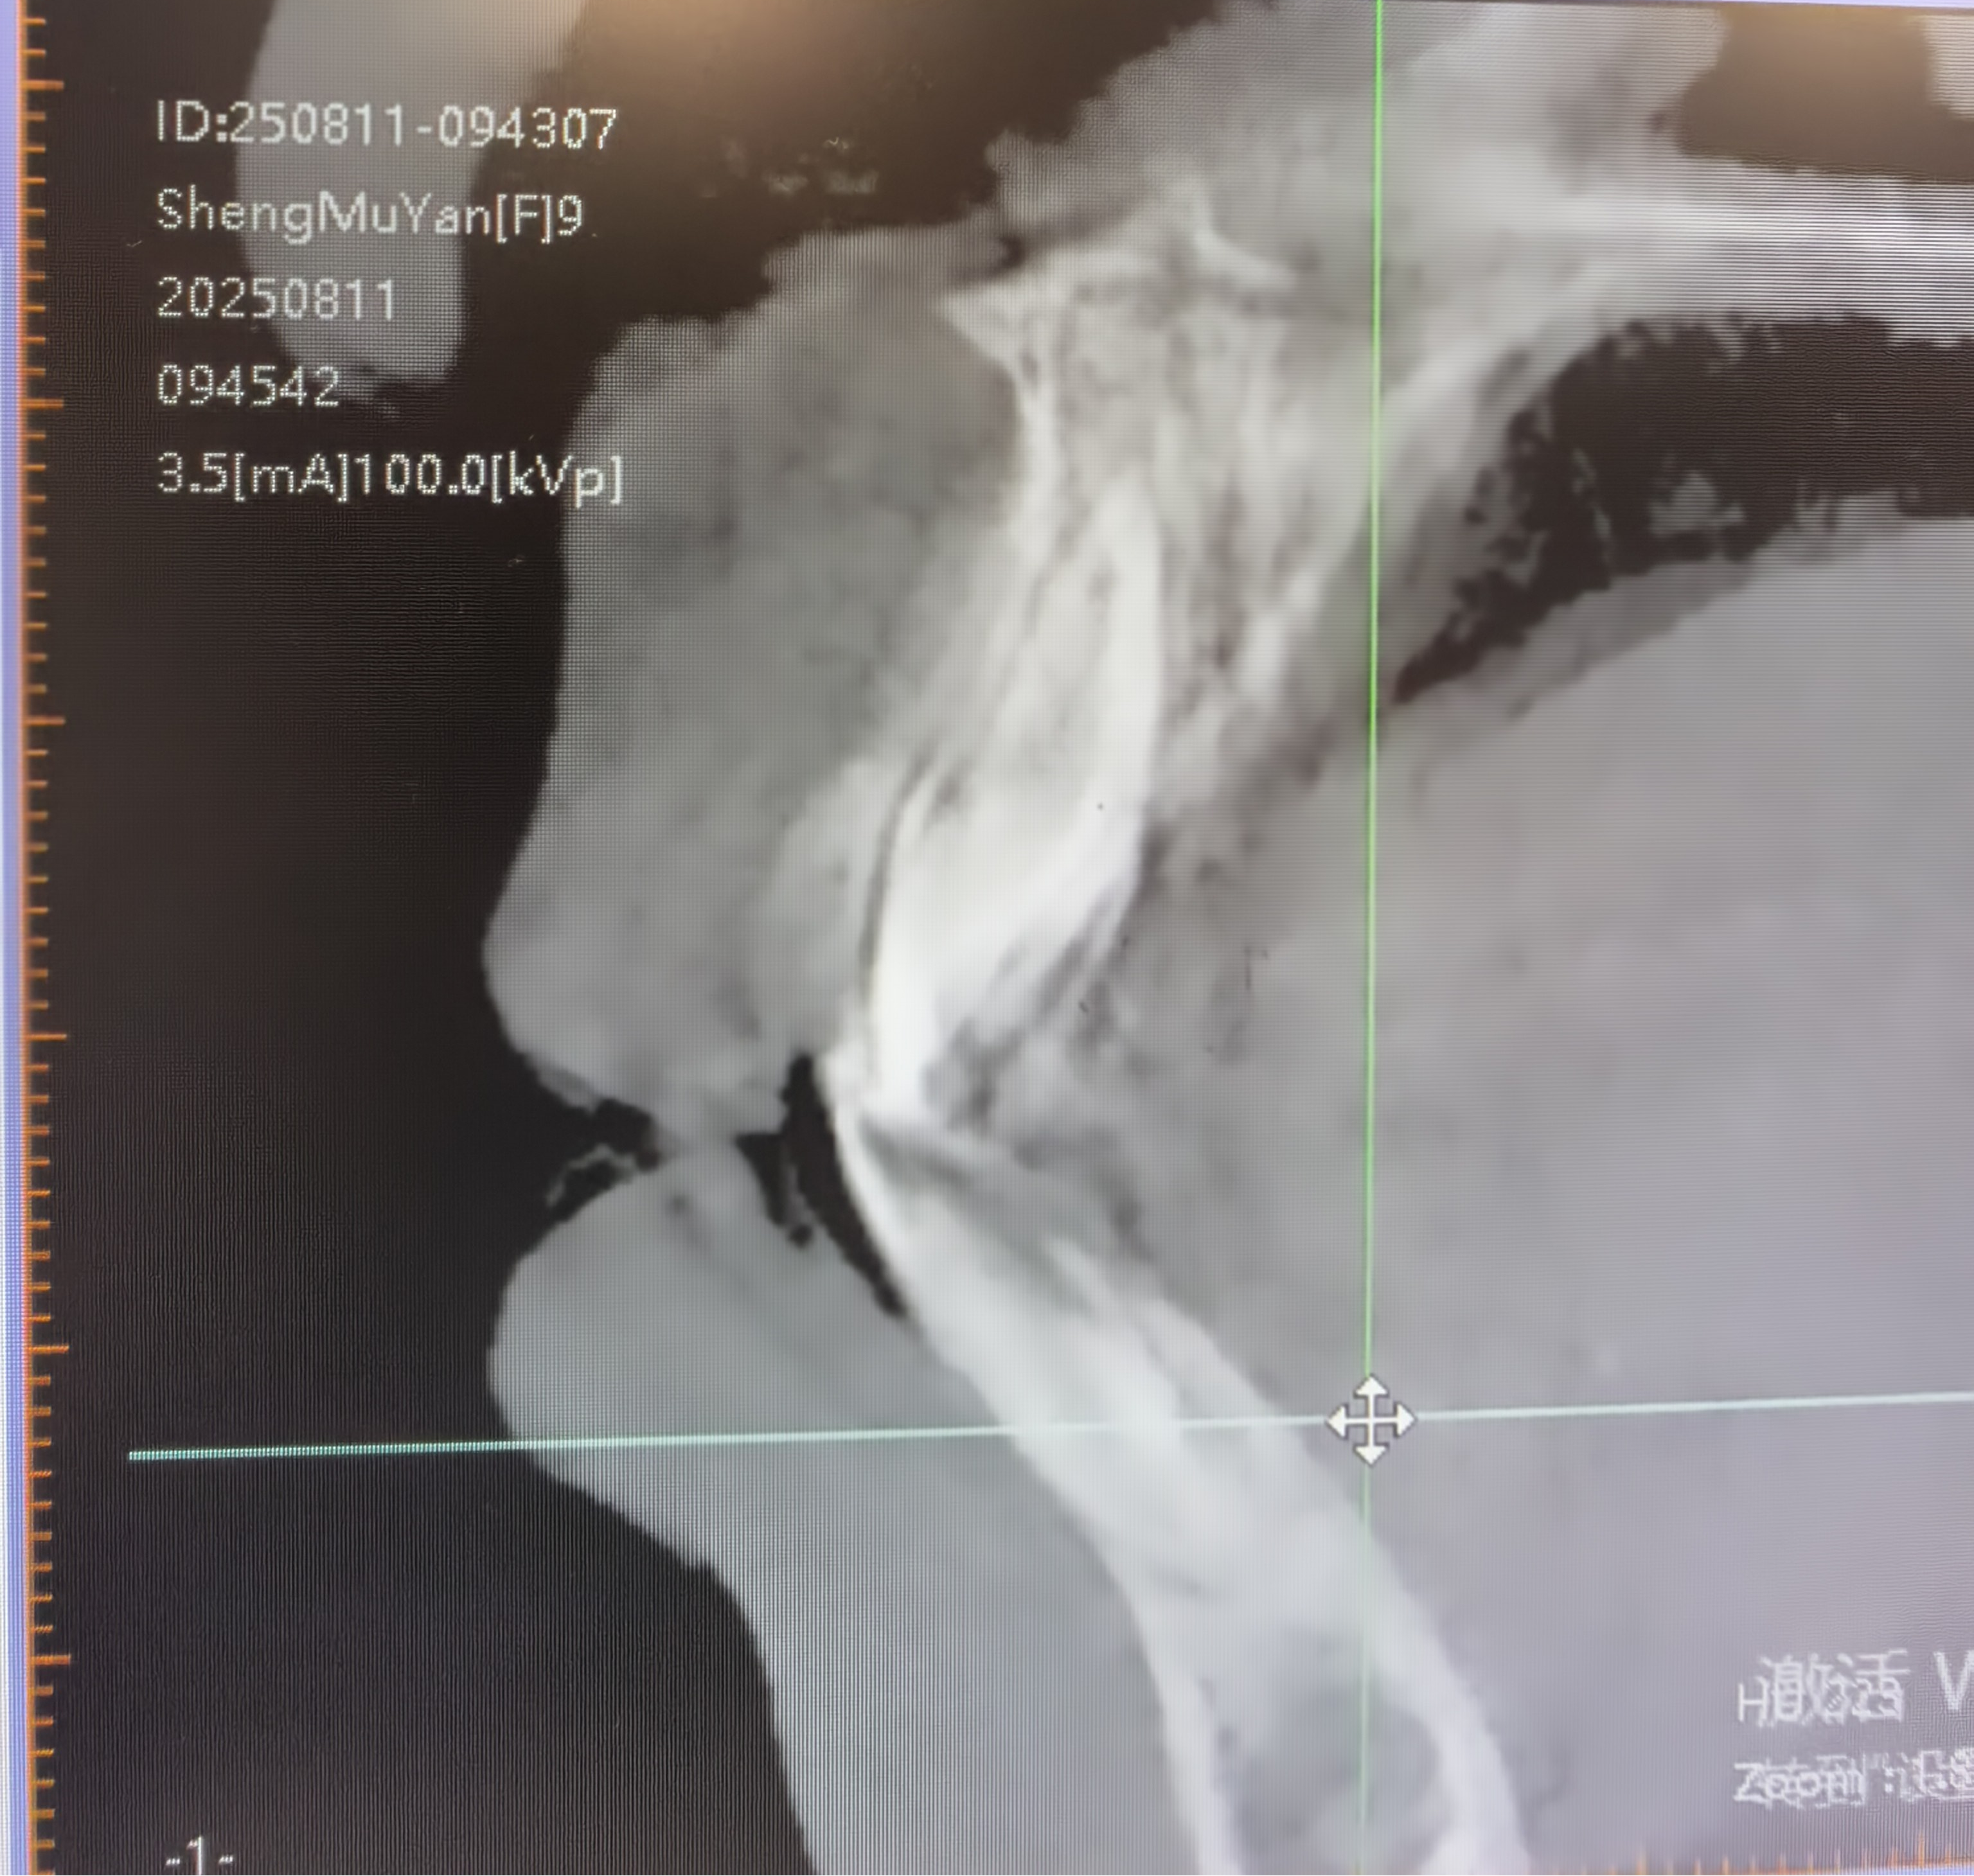

家长发现孩子面型呈轻度凹面型,下巴前突、鼻唇沟(法令纹)区域凹陷,随即到我院口腔中心就诊咨询。临床检查显示,患儿前牙反合、磨牙为三类关系,属于典型的骨性不协调;影像分析也明确了其颌骨与牙齿的三维异常关系。

矫治前 矫治后